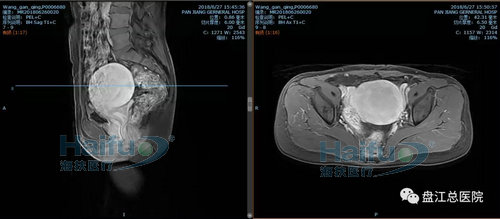

我院病例2:患者王XX,46岁,子宫腺肌症患者。

因“发现盆腔包块10+年,继发性痛经2+年”入院。于2018年6月28日行高强度聚焦超声消融治疗(HIFU)。

治疗经过:给予镇静镇痛药物后开始辐,患者诉稍有骶尾部及治疗区胀痛不适,余未诉有不适,安静休息配合治疗。总治疗时间25min。

术前磁共振增强横断位及矢状位,见病灶内明显强化

术后磁共振增强,见病灶内无明显强化,病灶发生凝固性坏死